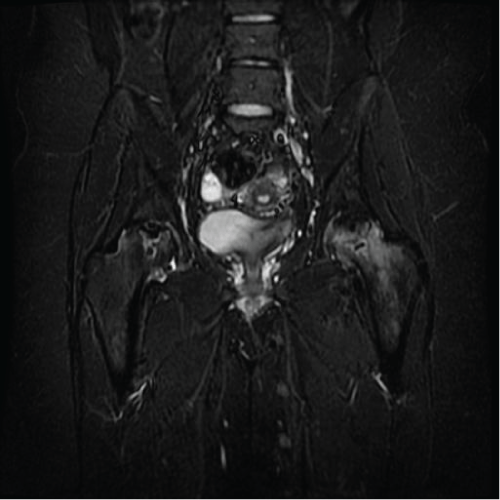

MG is a 31 yo F who presented with left hip pain for over a decade. MRI and radiographs had been obtained prior to presentation to our office which showed anterior quadrant cystic changes in the femoral head consistent with AVN in the pre-collapse state. On physical exam, the patient had excellent range of motion. The patient had already tried and failed conservative measures such as oral pain control, CSI, and protected weight bearing. She elected to undergo core decompression of the affected femoral head. At one year postoperatively she has limited improvement in her pain and continues to rehabilitate Figure 1, Figure 2, Figure 3, Figure 4 and Figure 5.

Figure 3: Preoperative coronal MRI. View Figure 3

Figure 4: Intraoperative radiograph. View Figure 4